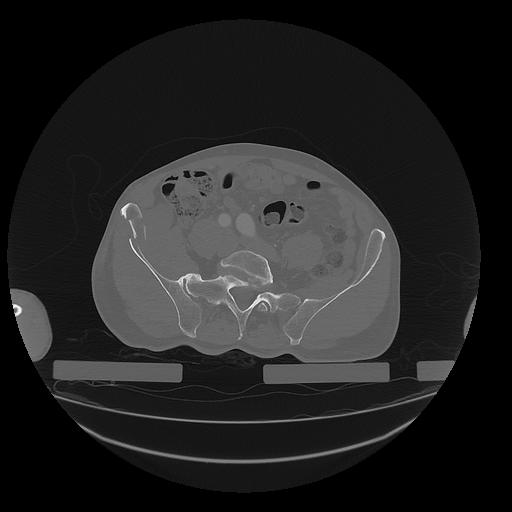

31 PULMON,CE,Vol,1.0,PULMON,,